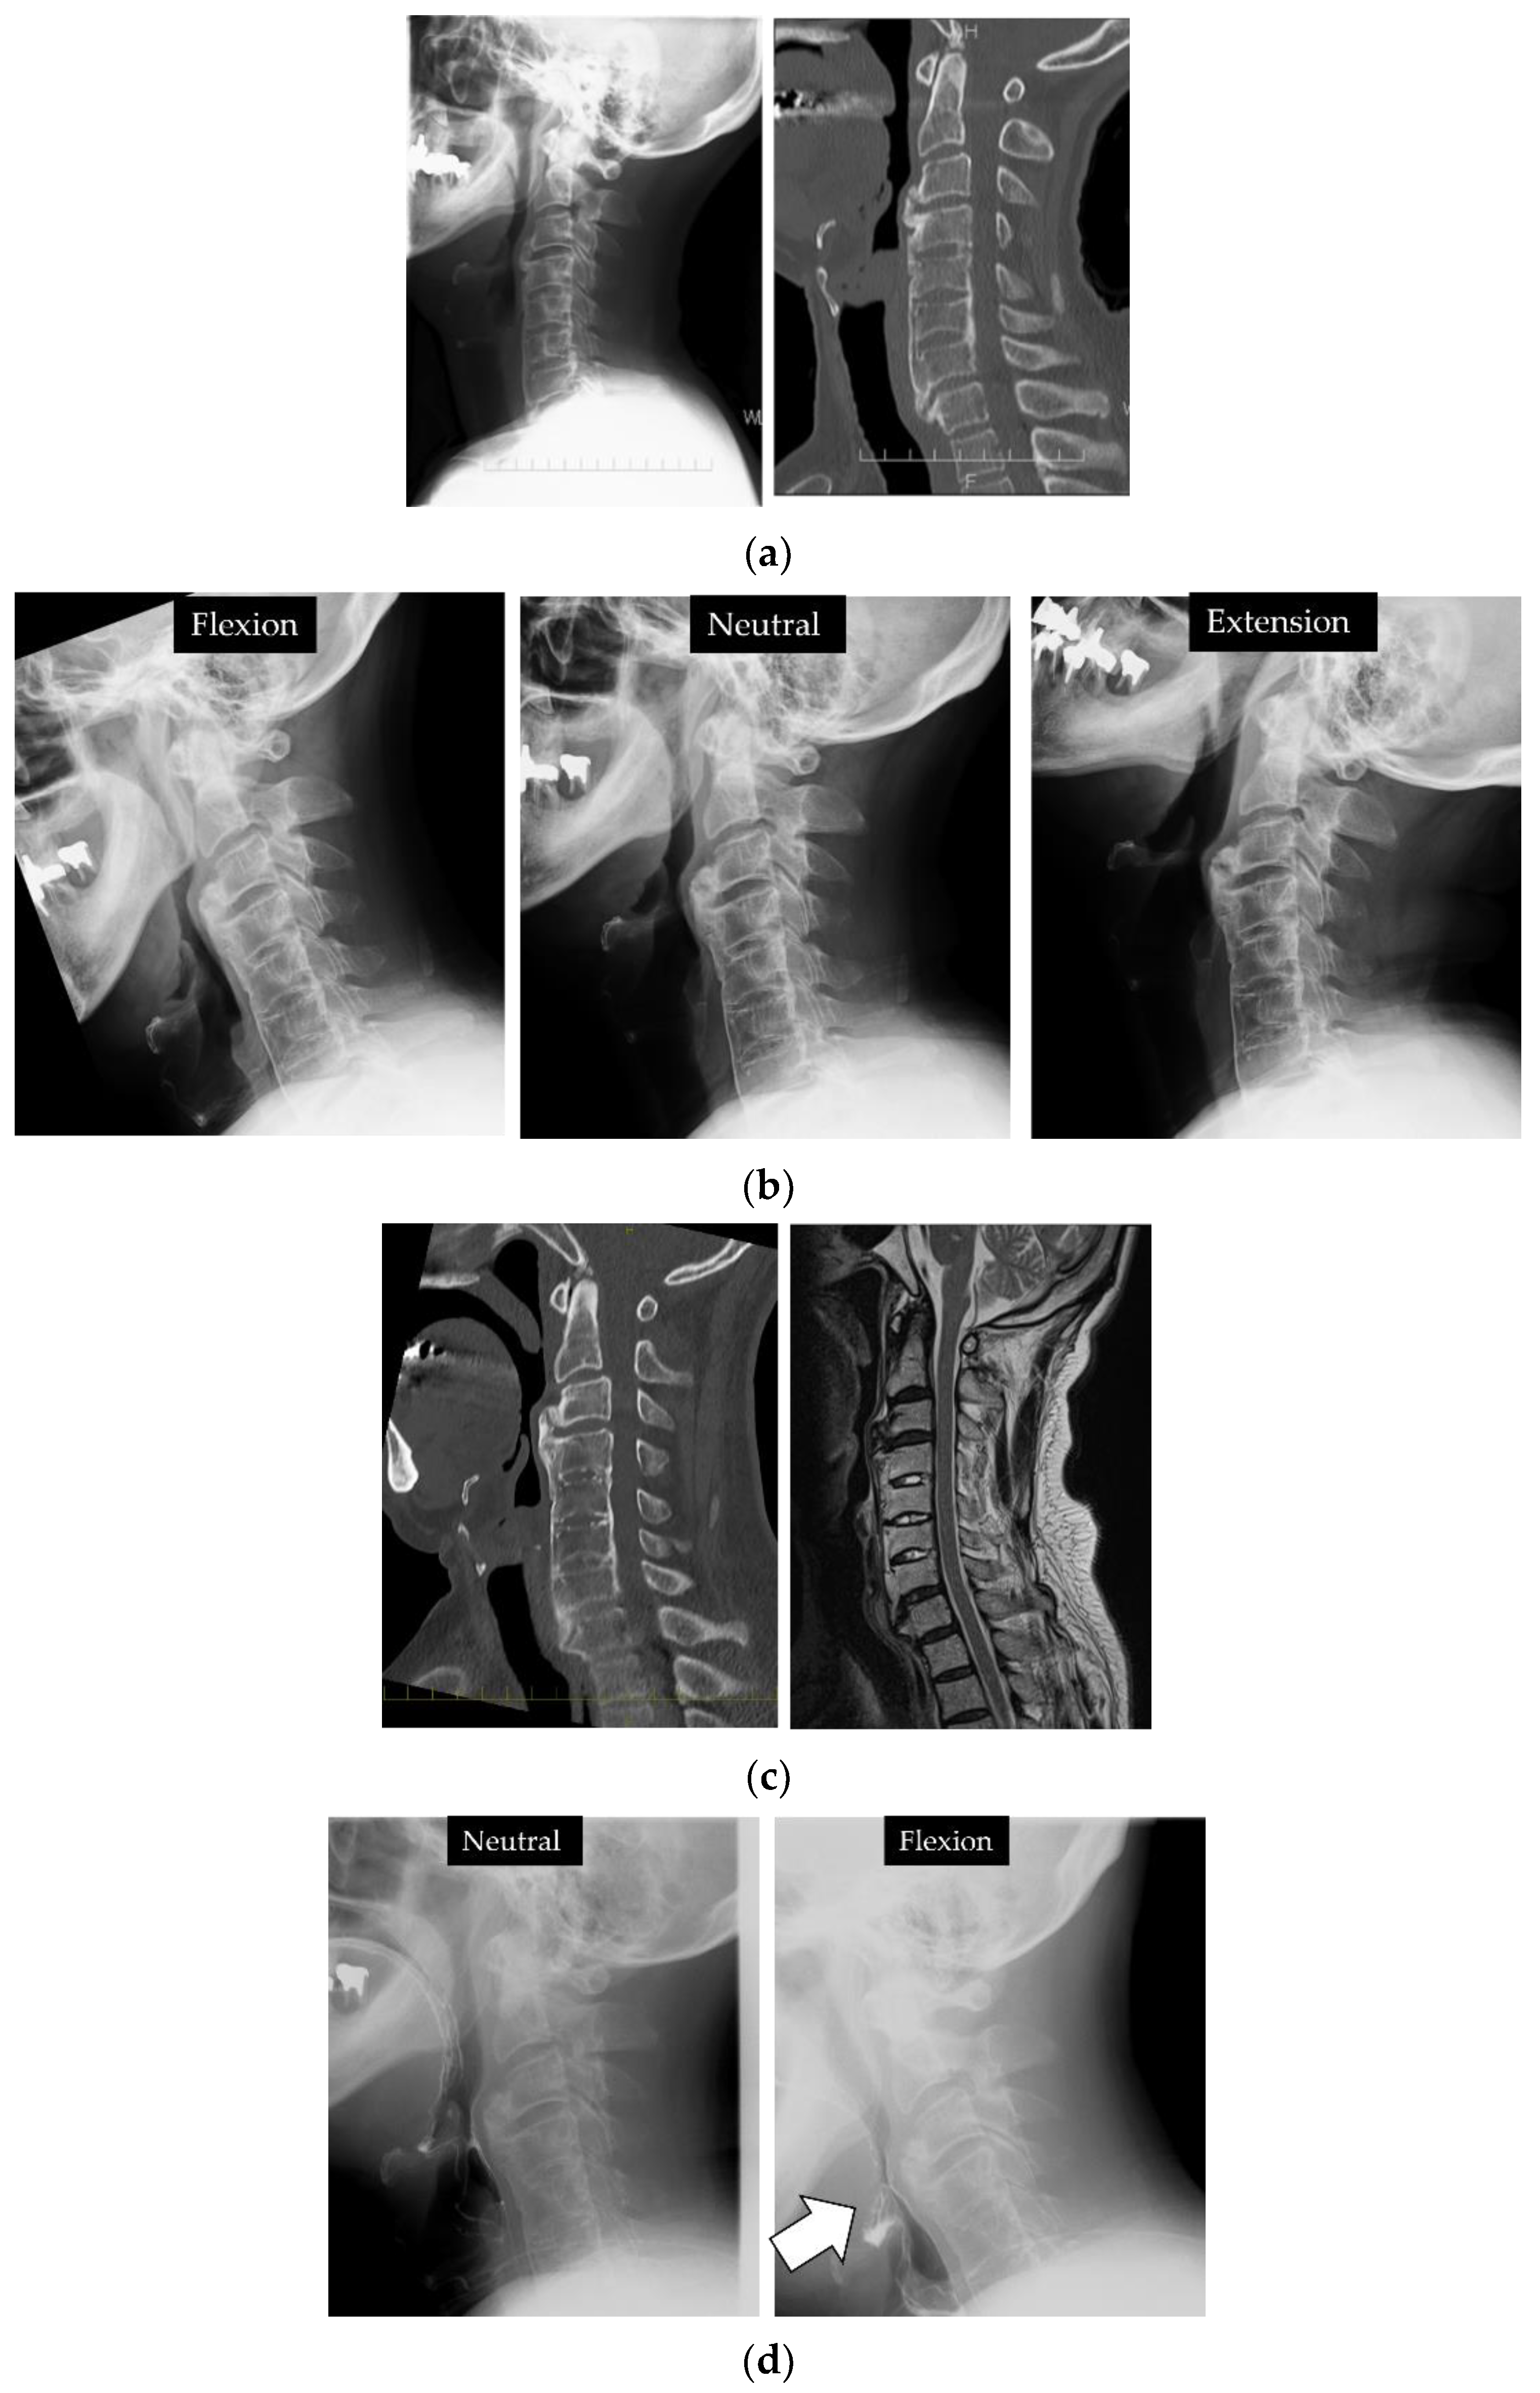

2.5. Clinical Presentations